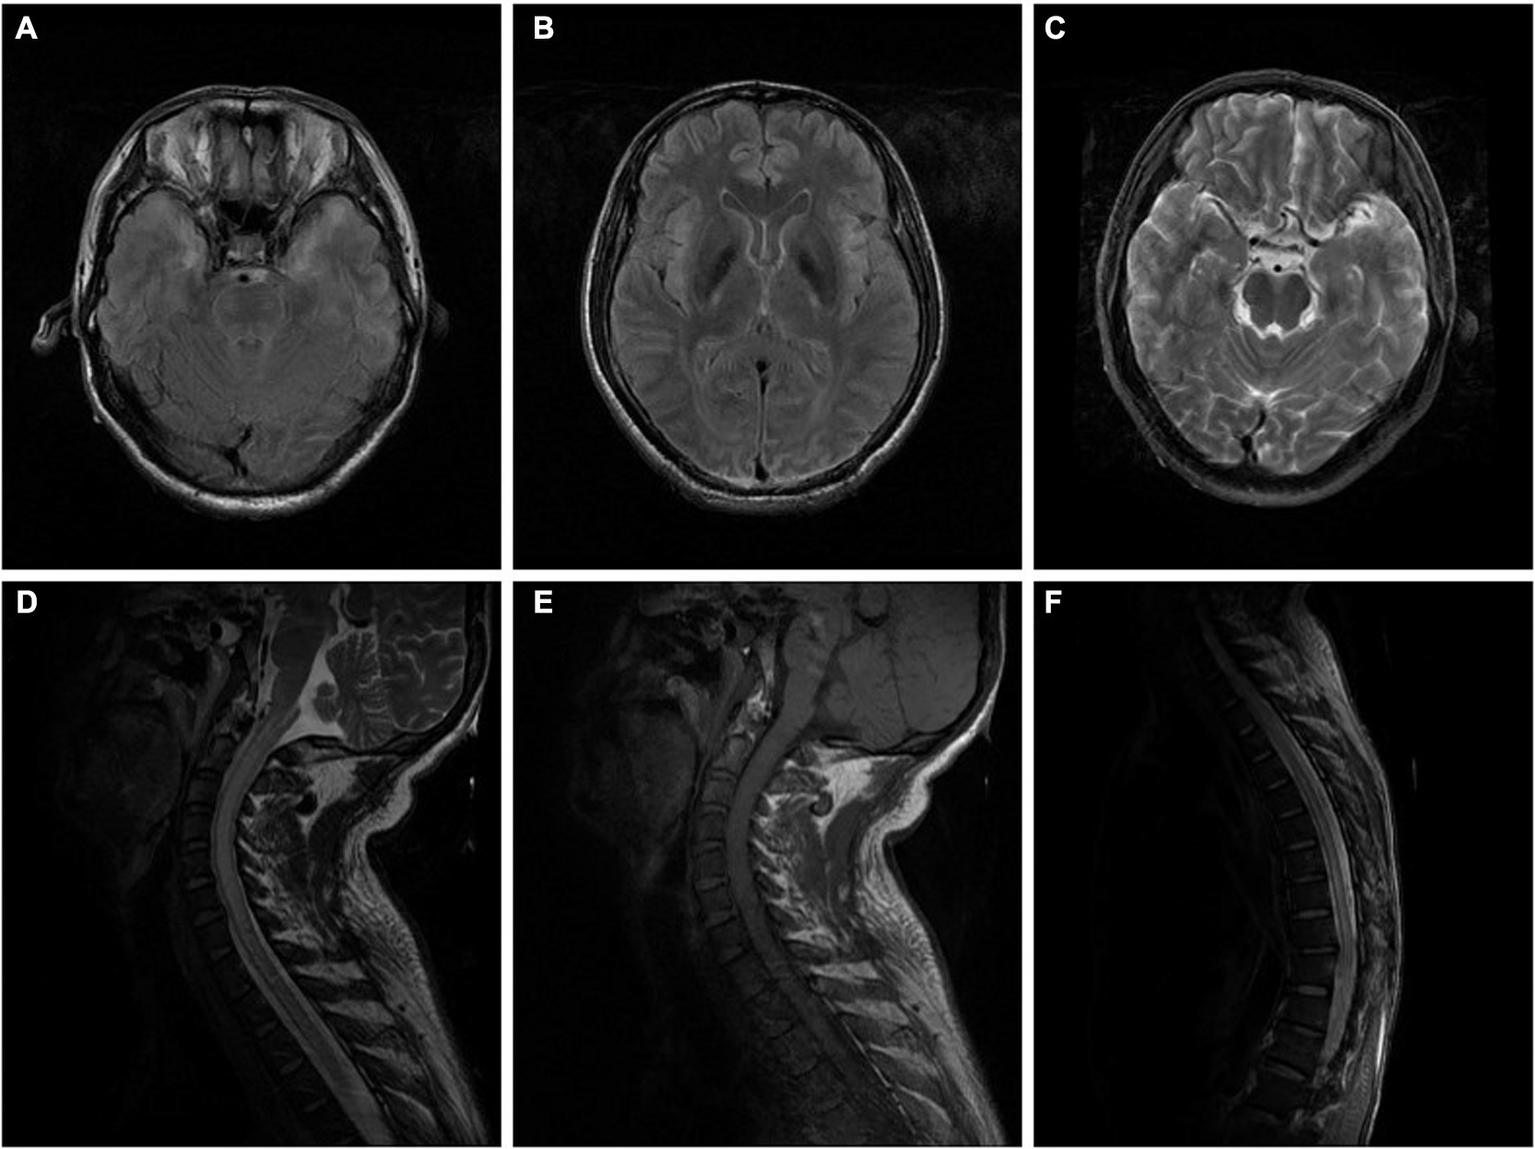

Figure 1

(A–C) Brain MRI of the patient in case 1 indicated high signal intensity of bilateral temporal lobes and insular cortex in a T2WI sequence performed without enhancement on a contrast-enhanced scan (10 days after onset). (D–F) Cervicothoracic MRI of the patient in case 1 showed extensive thickening of the cervical and thoracic spinal cord, especially the cervical spinal cord, and an increased signal intensity in T2WI sequence, with slightly patchy enhancement of the lesions on contrast-enhanced scan (10 days after onset).